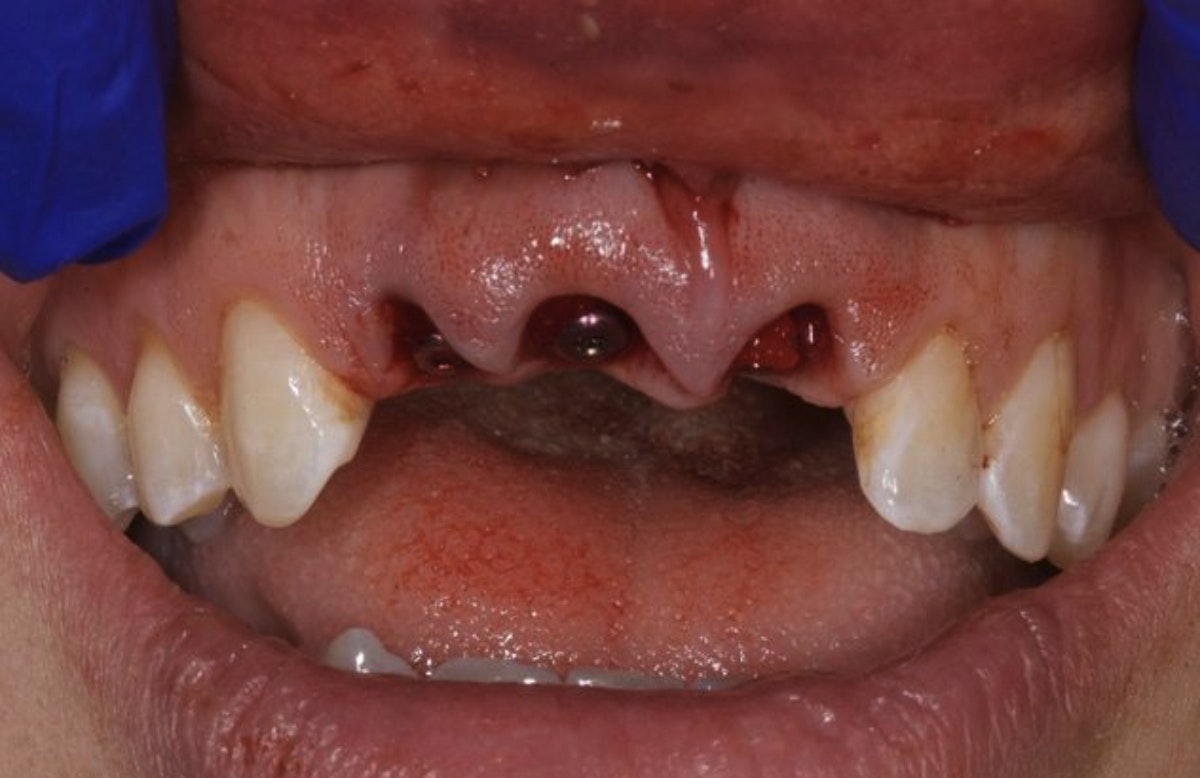

Patient missing three front teeth

Before

This patient lost multiple teeth in a scooter accident. We replaced their lost teeth with three implant-supported restorations. The result looks natural, didn't require crowning any teeth to support a traditional bridge, and will prevent the jaw atrophy that occurs in the absence of tooth roots.